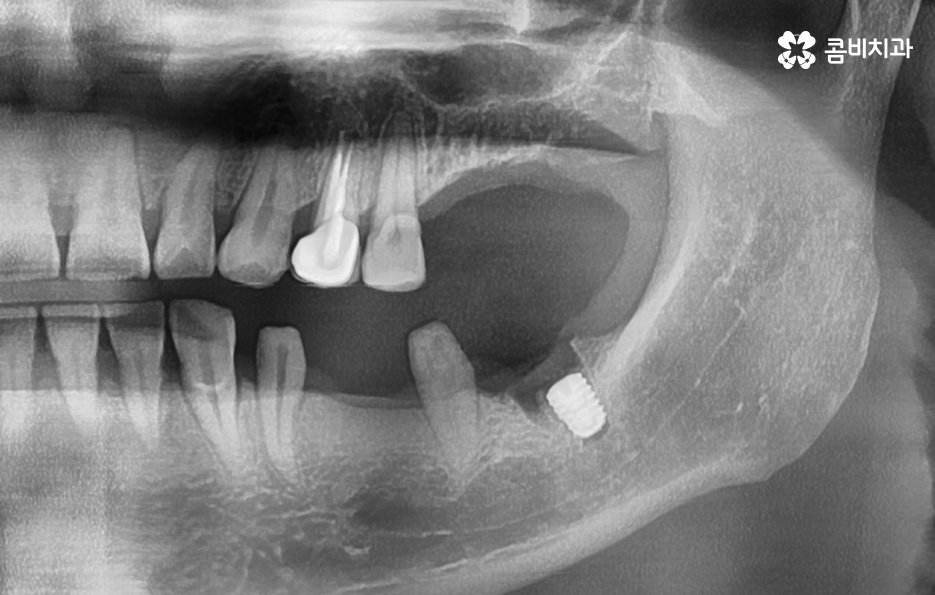

반면에 치주염이 심해져서 치조골이 녹아내리고 이미 치아의 뿌리가 보일 정도로 잇몸이 약해진 상태에는 치아 발치 후 잇몸이 충분히 회복한 뒤 임플란트를 식립할 수 있는 잇몸 뼈가 충분한지 확인 후 경우에 따라서는 뼈이식이 추가될 수 있는데요.

임플란트는 잇몸 뼈에 식립하기 때문에 치주염으로 인해 잇몸 뼈가 부족하거나 치아를 발치 후 오랜 시간이 지난 다음에 임플란트를 하게 될 경우 임플란트를 식립할 충분한 잇몸 뼈의 확보를 위해 뼈이식을 받아야 할 수 있어요

하지만 앞서 설명드린 것처럼 30대 이후에는 치주질환을 앓게 되는 분들이 급격히 늘어나며 치주질환 관리가 잘 안되신 분들의 경우 40대에도 치주염으로 인해 치아를 상당수 잃게 되는 사례도 적지 않게 확인되고 있어요